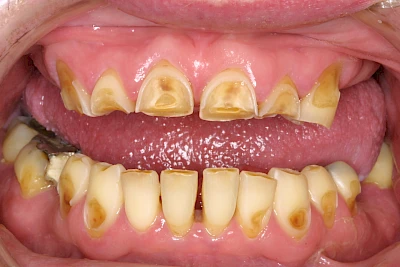

Auswaschung (Erosion) dagegen ist eine Verschleißerscheinung der Zähne aufgrund von immer wiederkehrenden Säureangriffen durch die Nahrung, verstärkt zum Beispiel durch den Genuss säurehaltiger Getränke oder Speisen. Auch bei Menschen mit einer Essstörung (z. B. Bulimie) können die Zähne durch die Magensäure ausgewaschen erscheinen.

Eine Sonderform sind sogenannte keilförmige Defekte im Bereich der Zahnhälse. Hier geht man davon aus, dass Knirschen und Pressen in Kombination mit falschen Putzgewohnheiten (zu hoher Putzdruck, Verwendung von Zahnpasta mit hohen Abrasionswerten) eine Rolle spielen.